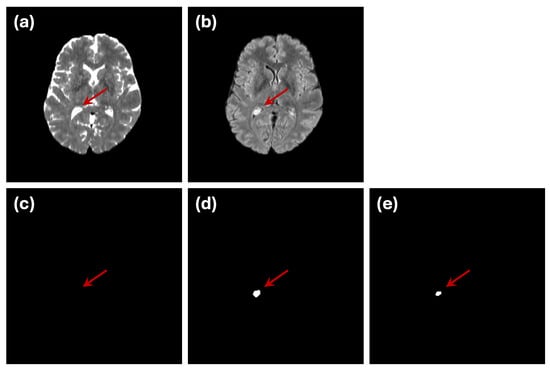

3.1. Image Dataset

5.3. Limitations